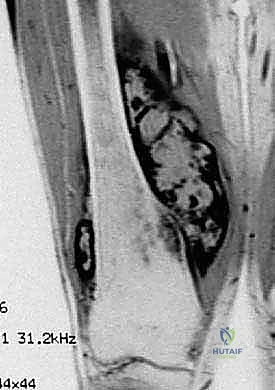

- التصوير بالرنين المغناطيسي (MRI): لتحديد الامتداد الدقيق للورم داخل العظم وفي الأنسجة الرخوة المحيطة (العضلات، الأوعية الدموية).

معرض الحالات الإشعاعية: توثيق النجاح الطبي مع د. محمد هطيف

الصور الإشعاعية قبل وبعد الجراحة هي الدليل القاطع على دقة ونجاح الإجراء الطبي. نستعرض هنا مجموعة من الصور التي توضح حجم الإنجاز الطبي في استبدال العظم المصاب بمفصل معدني متطور.